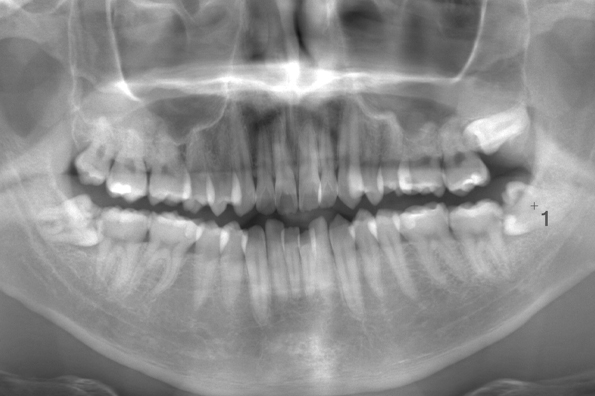

CASE 10

| 年齢・性別 | 39歳・男性 |

|---|---|

| 主訴 | 左上下親知らず抜きたい |

| 抜歯期間 | 30分 |

| 抜歯費用 | 約2,500円(保険内) 別途CT撮影で3,000円 (2022年7月現在) |

| 抜歯内容 | 左上下の親知らず抜歯 |

| 治療方針 |

親知らずは抜いたほうが良い認識はあったものの、痛みや腫れが出ることを知って、勇気が出ないままでいたとのことでした。 そのまま放置していたら虫歯になってしまい、今回ご来院されました。しっかりと麻酔をして緊張をほぐしながら抜歯を始めました。完全萌出のため、時間を要することなくすぐに抜歯することができました。 |